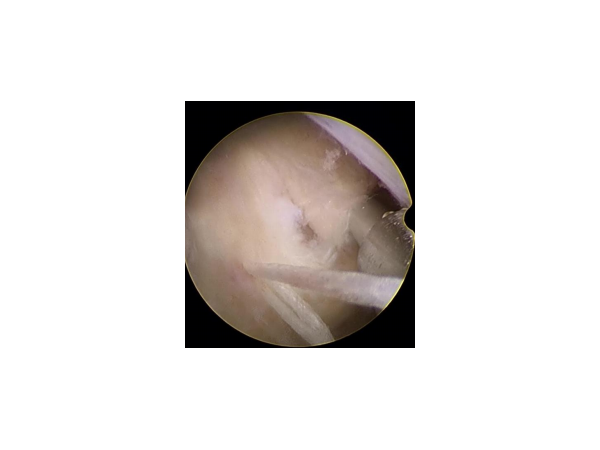

產(chǎn)品說明:一次性纖維環(huán)縫合器技術(shù)的意義在于:1、纖維環(huán)縫合術(shù)是把造成椎間盤突出癥狀的病因,即損壞的纖維環(huán)修復(fù)上。椎間盤突出的根本原

產(chǎn)品說明:杭州歸創(chuàng) 一次性使用纖維環(huán)縫合器產(chǎn)品賣點(diǎn):脊柱科專用!無競(jìng)爭(zhēng),高利潤(rùn),市場(chǎng)潛力巨大!山東省招商實(shí)力廠家,知名品牌,資質(zhì)齊全,

產(chǎn)品說明:骨科浙江歸創(chuàng)一次性纖維環(huán)縫合器廠家:在纖維環(huán)縫合器沒出現(xiàn)之前,醫(yī)生為了降低椎間盤突出復(fù)發(fā)的風(fēng)險(xiǎn),都會(huì)盡量把髓核清理干凈。

產(chǎn)品說明:浙江歸創(chuàng)一次性纖維環(huán)縫合器:隨著醫(yī)學(xué)技術(shù)進(jìn)步,腰椎間盤突出髓核摘除術(shù)后,纖維環(huán)缺口的閉合問題,已經(jīng)不再是難題。纖維環(huán)縫合

產(chǎn)品說明:一次性纖維環(huán)縫合器的介紹:一次性纖維環(huán)縫合器,以在一個(gè)狹小的通道內(nèi)完成對(duì)深部組織或切口的自動(dòng)縫合,以大限度地避免人為因素

產(chǎn)品說明:一次性纖維環(huán)縫合器適應(yīng)癥 禁忌癥:一次性纖維環(huán)縫合器適用癥:1、非椎間盤髓核摘除手術(shù)患者及開放手術(shù)下用2、椎間盤髓核摘除術(shù)后

產(chǎn)品說明:一次性纖維環(huán)縫合修復(fù)的意義:1 有效降低髓核摘除術(shù)后復(fù)發(fā)率2、減少纖維環(huán)瘢痕形成3、降低髓核炎性介質(zhì)對(duì)神經(jīng)根的刺激4、纖維環(huán)

產(chǎn)品說明:一次性纖維環(huán)縫合器的臨床應(yīng)用:隨著纖維環(huán)縫合器縫合纖維環(huán)技術(shù)的推廣,很多學(xué)者做了相關(guān)的臨床研究。Parker等對(duì)30例纖維環(huán)縫合

產(chǎn)品說明:纖維環(huán)縫合技術(shù)臨床意義:1、纖維環(huán)縫合術(shù)是對(duì)造成椎間盤突出癥狀的病因,即損壞的纖維環(huán)進(jìn)行修復(fù)。椎間盤突出的根本原因被治療

產(chǎn)品說明:一次性纖維環(huán)縫合器國(guó)內(nèi)品牌介紹:目前國(guó)內(nèi)一次性纖維環(huán)縫合器品牌:歸創(chuàng)通橋一次性纖維環(huán)縫合器,醫(yī)術(shù)苑推廣一次性纖維環(huán)縫合器